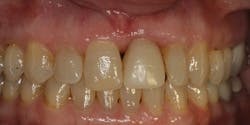

After following the case for 18 months, the periodontal condition appeared stable and the patient elected to replace the temporary crown on No. 9 and do some cosmetic work at the same time on teeth Nos. 6 through 11. (Figs. 7 &8) .

Fig. 7 Crowns 6 through 11

Fig. 8 Full-face